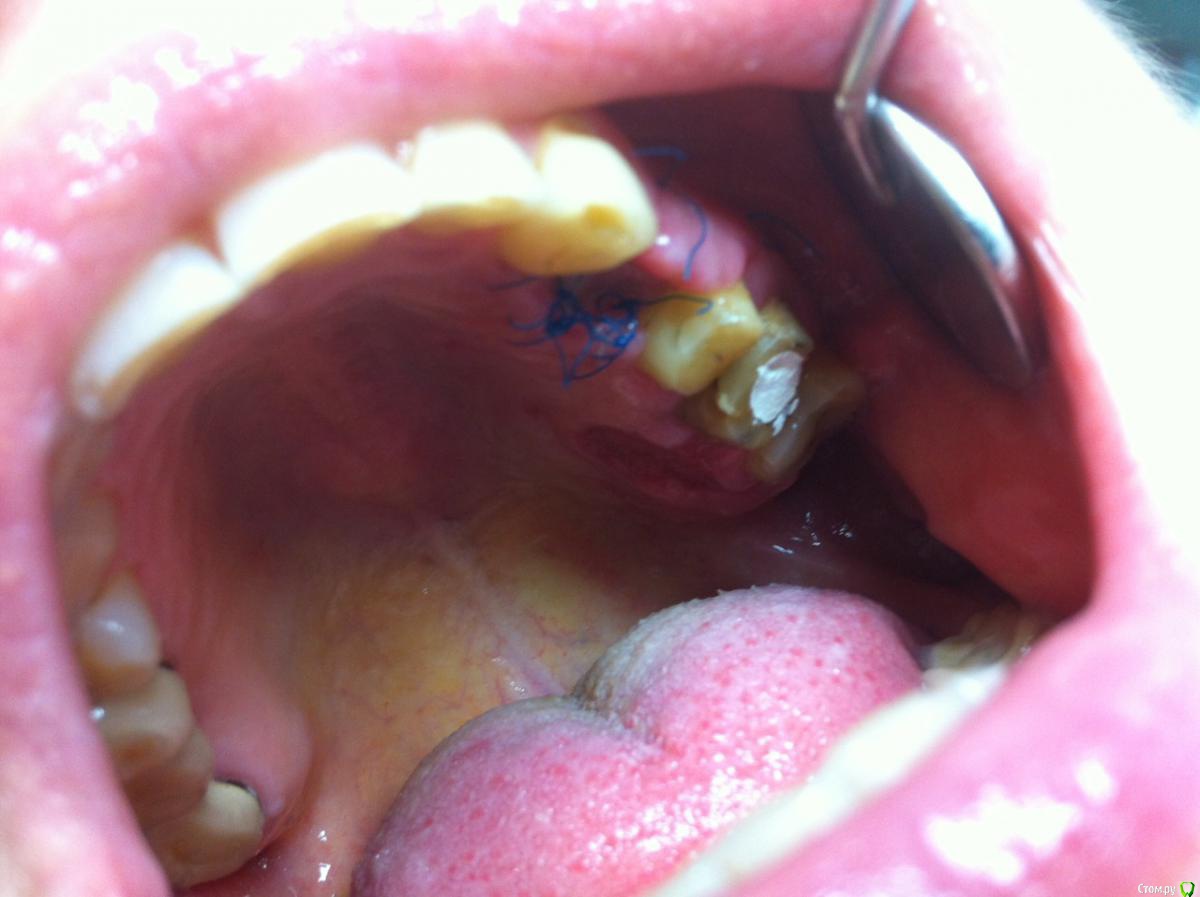

L.E.S.I.K. Опубликовано 25 августа, 2015 Поделиться Опубликовано 25 августа, 2015 22 августа проведена имплантация в область 2.4 (3,3*10), торк около 40, оголенный виток c небной поверхности закрыт ауто, поверх ССТ. Сегодня вот такая картина.(приношу извинения за качество фото-снимал коллега на телефон.) Сам пациентку смогу увидеть только в пятницу. Как быть? Предполагаю несколько вариантов: 1.Убрать некротизированный сст, установить формирователь,2 убрать некроз, сделать VIP CT.3 полоскания хлоргексидином, ждать эпителизации Как быть? Ссылка на комментарий

Тимур86 Опубликовано 25 августа, 2015 Поделиться Опубликовано 25 августа, 2015 там некроз или фибрин?не видно Ссылка на комментарий

L.E.S.I.K. Опубликовано 25 августа, 2015 Автор Поделиться Опубликовано 25 августа, 2015 К сожалению, сам не знаю, пациентку не видел, сейчас в отпуске. Но думаю, что некроз, т.к ССТ уложен на кость, а лоскут "сполз", врял ли сосуды проросли. Ссылка на комментарий

L.E.S.I.K. Опубликовано 28 августа, 2015 Автор Поделиться Опубликовано 28 августа, 2015 Сегодня осмотрел пациентку. Винт на визуализируется - в ране гранулирующий сст. Снял швы, отправил полоскать. Всем спасибо за помощь. Ссылка на комментарий